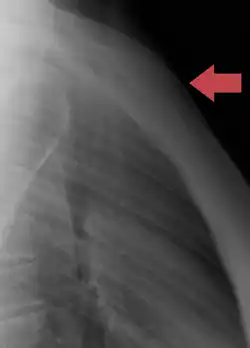

In its natural position, the sternum is angled obliquely, downward and forward. It is slightly convex in front and concave behind; broad above, shaped like a "T", becoming narrowed at the point where the manubrium joins the body, after which it again widens a little to below the middle of the body, and then narrows to its lower extremity. It is usually longer in the male than in the female.[3]